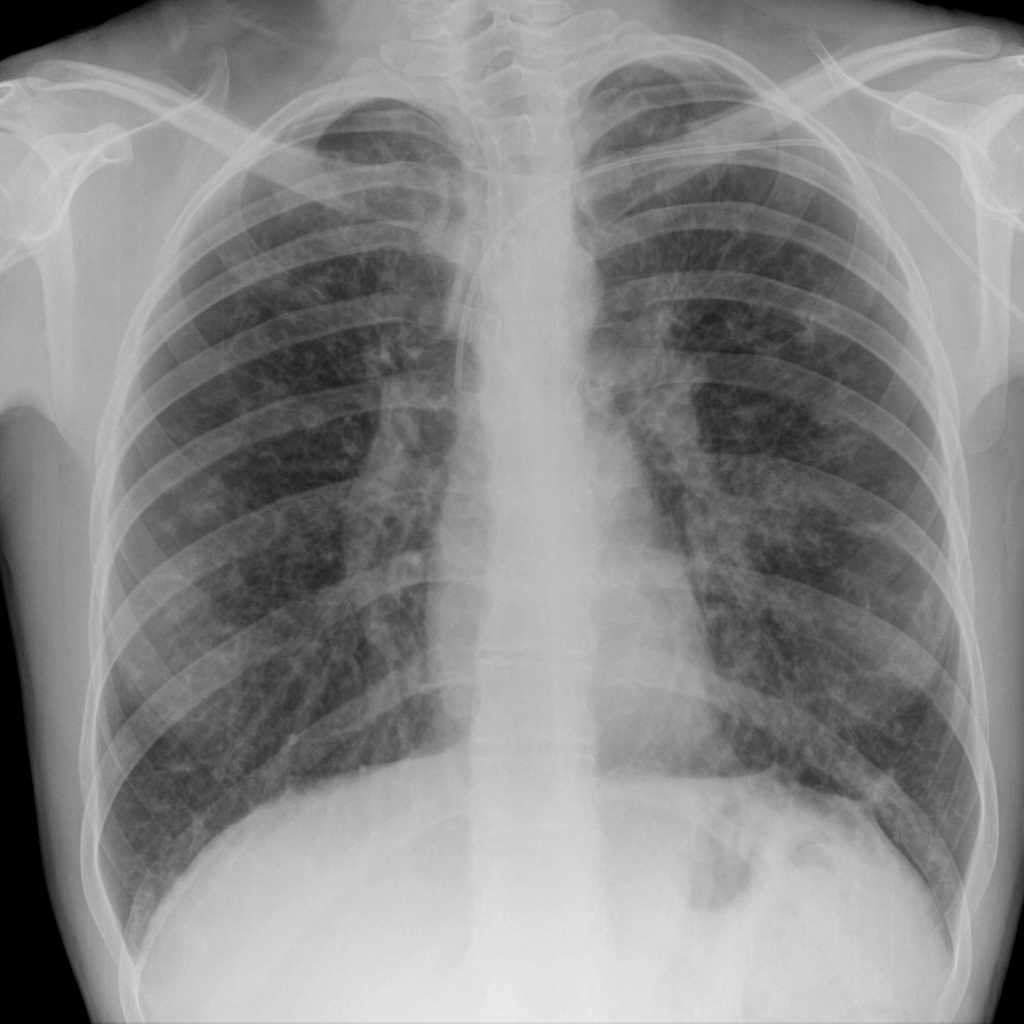

Example 5

Diagnosis

Median Sternotomy Wires